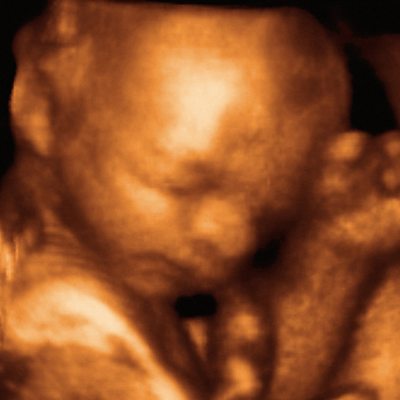

On the 10th May 1981 a baby was born after having been successfully operated on whilst still in the womb. The paediatric surgeon who developed the technique was Dr Michael Harrison. He has been speaking to Ashley Byrne about the challenges he faced. Photo: an ultrasound of a foetus in the womb. Credit: Science Photo Library.